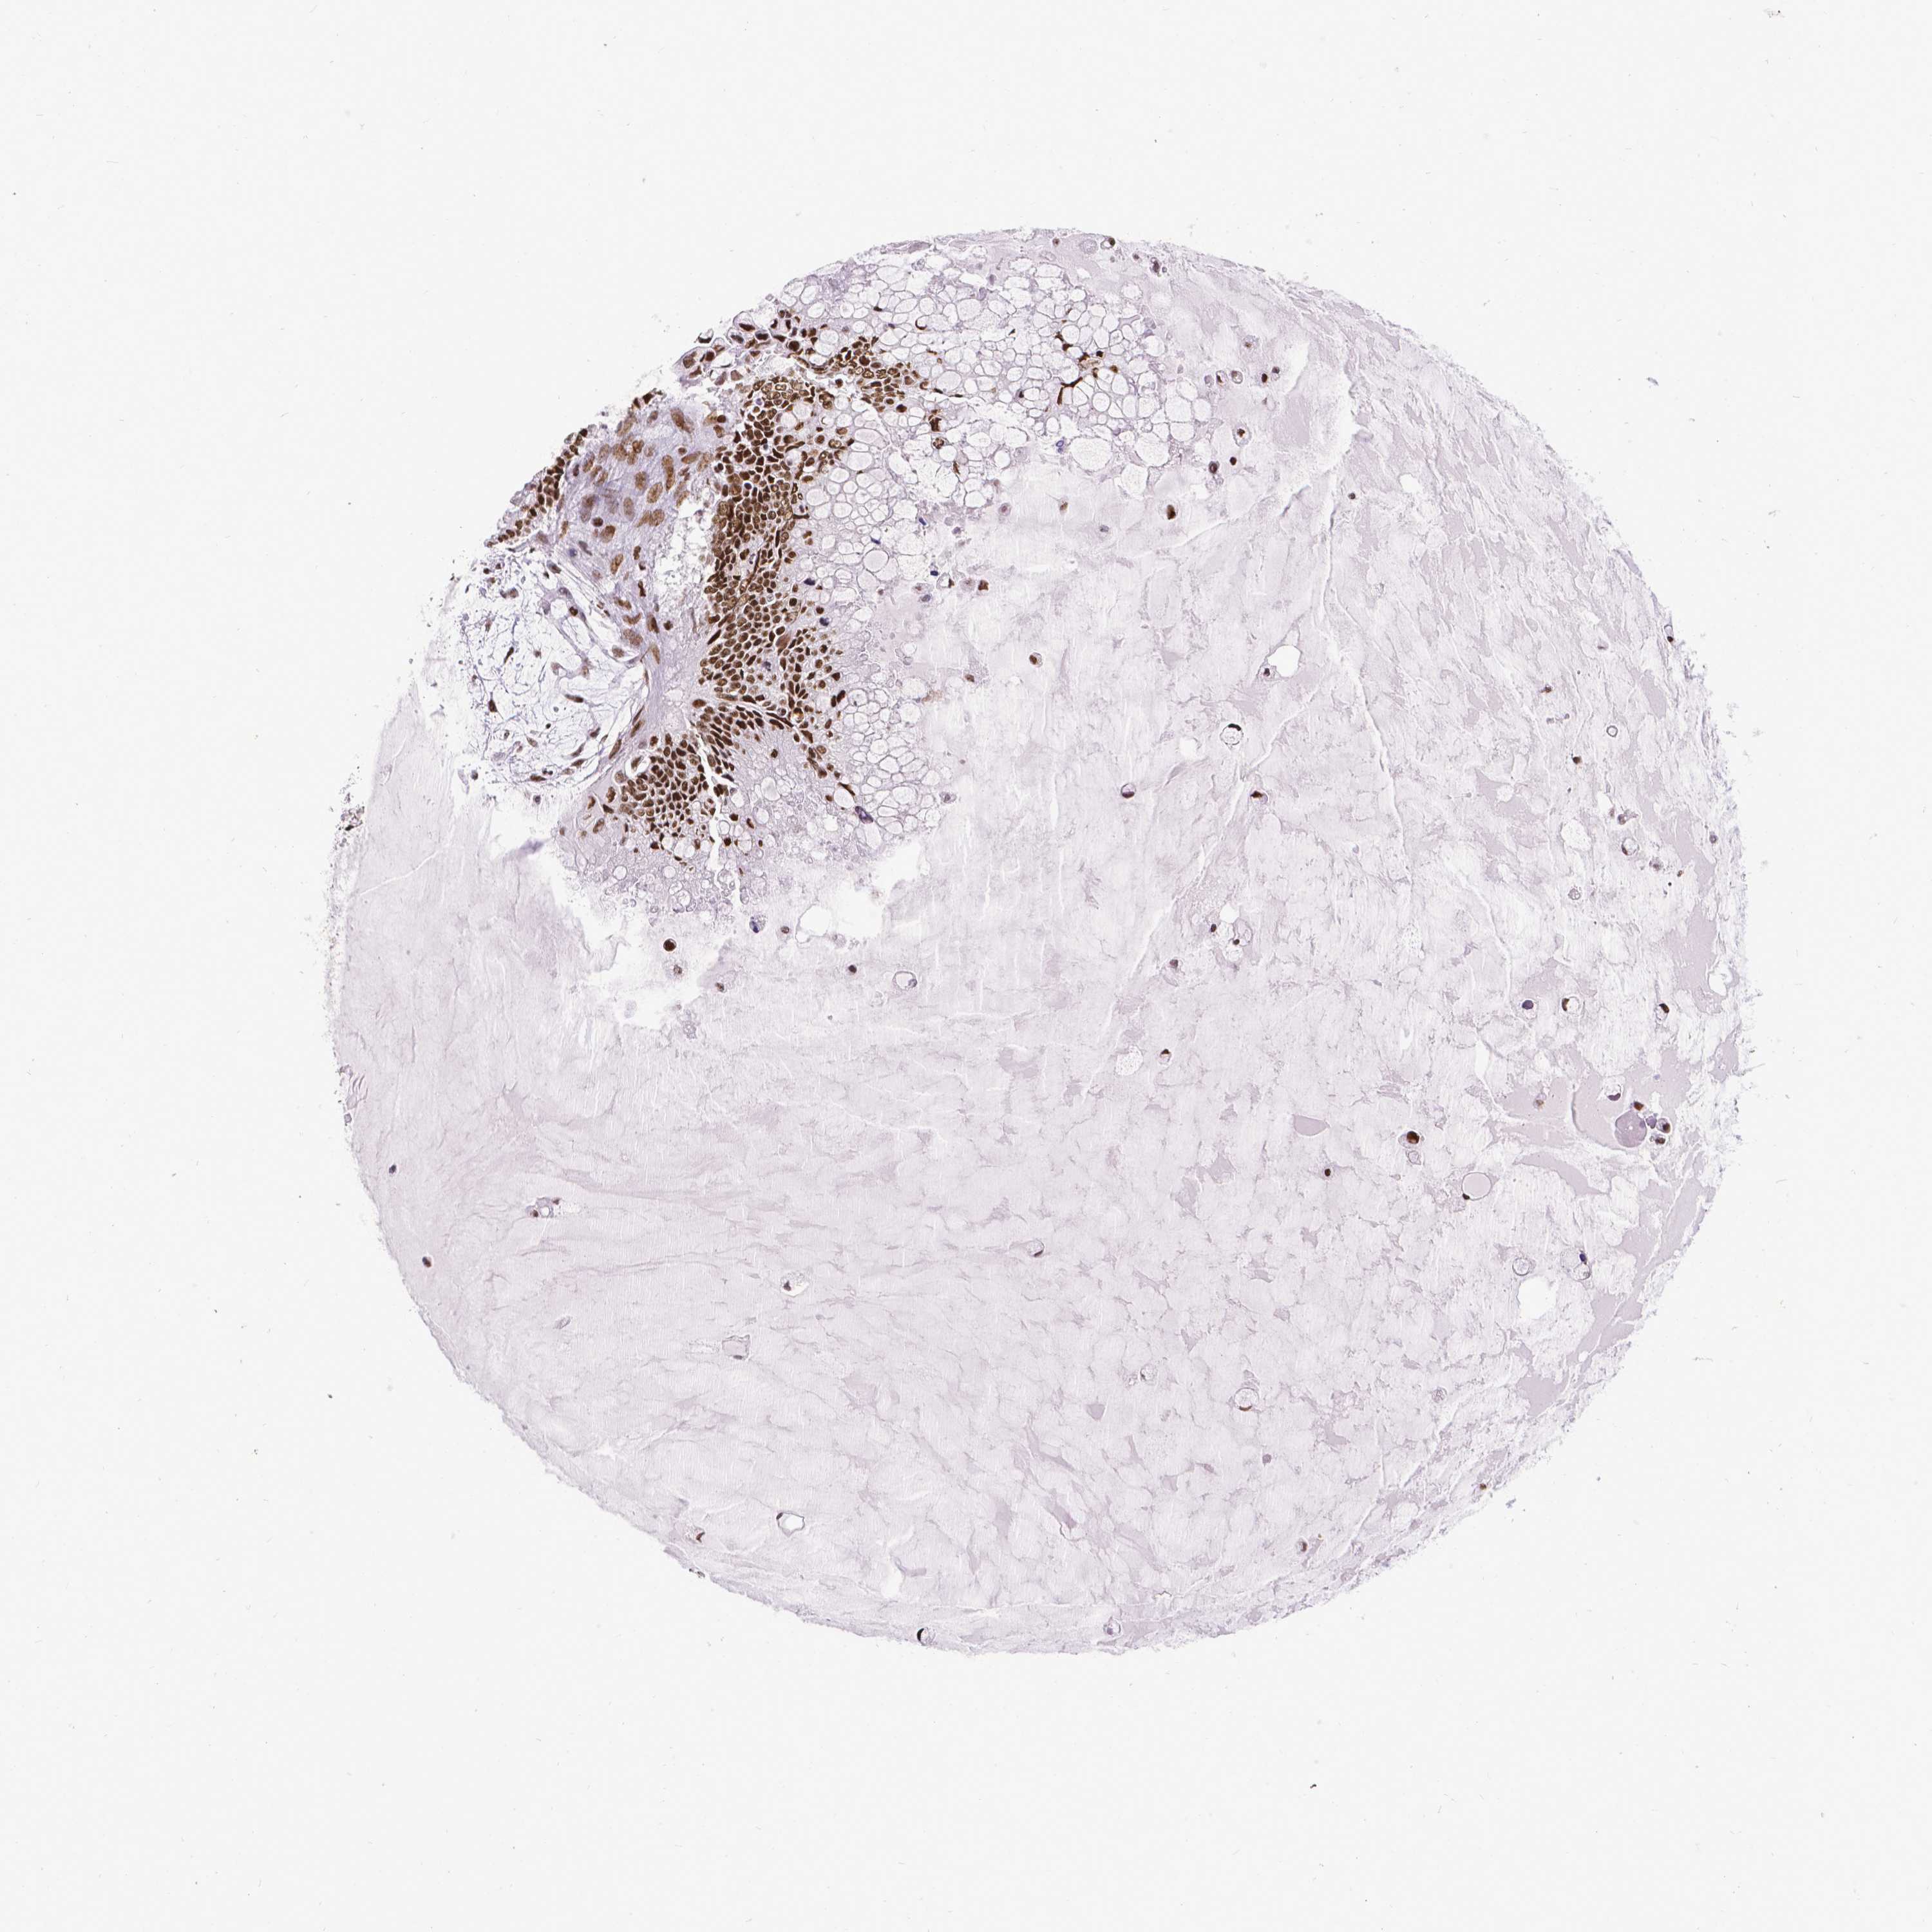

OVARIAN CANCER - Protein expressioni

A mouse-over function shows sample information and annotation data. Click on an image to view it in a full screen mode. Samples can be filtered based on level of antibody staining by selecting one or several of the following categories: high, medium, low and not detected. The assay and annotation is described here.

Note that samples used for immunohistochemistry by the Human Protein Atlas do not correspond to samples in the TCGA dataset.

Antibody stainingi

Antibody staining in the annotated cell types in the current human tissue is reported as not detected, low, medium, or high, based on conventional immunohistochemistry profiling in selected tissues. This score is based on the combination of the staining intensity and fraction of stained cells.

Each image is clickable and will lead to virtual microscopy that enables deeper exploration of all samples and also displays staining intensity scores, fraction scores and subcellular localization as well as patient and tissue information for each sample.

Antibody HPA004122

Cystadenocarcinoma, serous, NOS